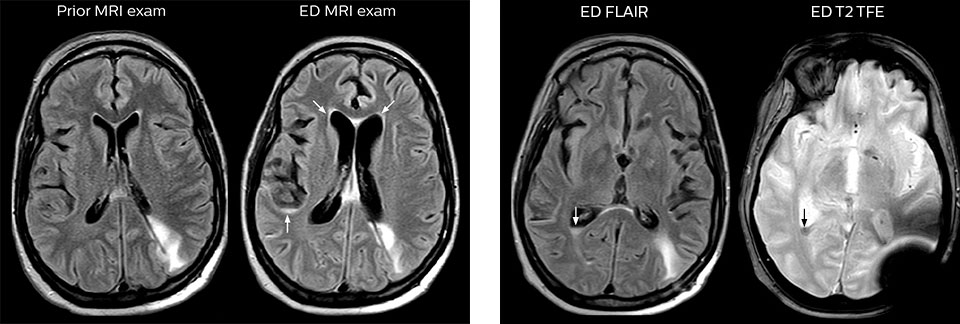

This patient presented with headache that was worse with neck flexion and we see a Chiari 1 malformation with low-lying cerebellar tonsils as well as some degenerative cervical thrombolytic change.